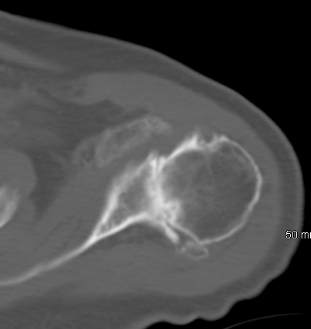

In the case example provided below a preoperative CT scan demonstrates no glenoid deformity and implantation of a anchored pegged glenoid component was performed without penetration of the glenoid vault. It seems that pressurization of the cement in intact glenoid vault would be ideal if there is no cortex penetration. Although it is critical when keeled glenoid components are used it seems that it has no implications when anchored pegged glenoid components are used. The reason is that we do not use cement for the central peg. In case of penetration it seems that for the central anchored ingrowth peg there will be "bicortical fixation".

![]() |

| Central anchored peg contained in the glenoid vault |